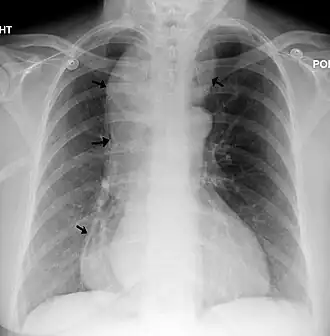

Raio X de um esôfago amplamente dilatado.

Com a perda do tônus da sua parede muscular e a dificuldade da passagem dos alimentos através da cárdia ocorre progressiva dilatação e alongamento do corpo esofágico, podendo formar uma grande câmara retroesternal contendo grandes volumes de alimento e saliva.

O diagnóstico nas fases iniciais pode ser difícil, já que a dilatação esofágica (mega esôfago) pode ainda não estar presente. Nesses casos os exames de rotina como endoscopia digestiva alta e o RX contrastado do tubo digestivo alto podem ser normais. Com a evolução da doença, o esôfago acaba por se dilatar e aí a endoscopia pode detectar a presença dessa dilatação e de resíduos alimentares retidos no esôfago. Já o RX contrastado de esôfago mostra a dilatação esofágica e nos casos mais avançados o alongamento e tortuosidade do corpo esofágico. Nas fases iniciais quando ainda não se identificam alterações anatômicas significativas, a esofagomanometria é o exame de escolha para o diagnóstico.